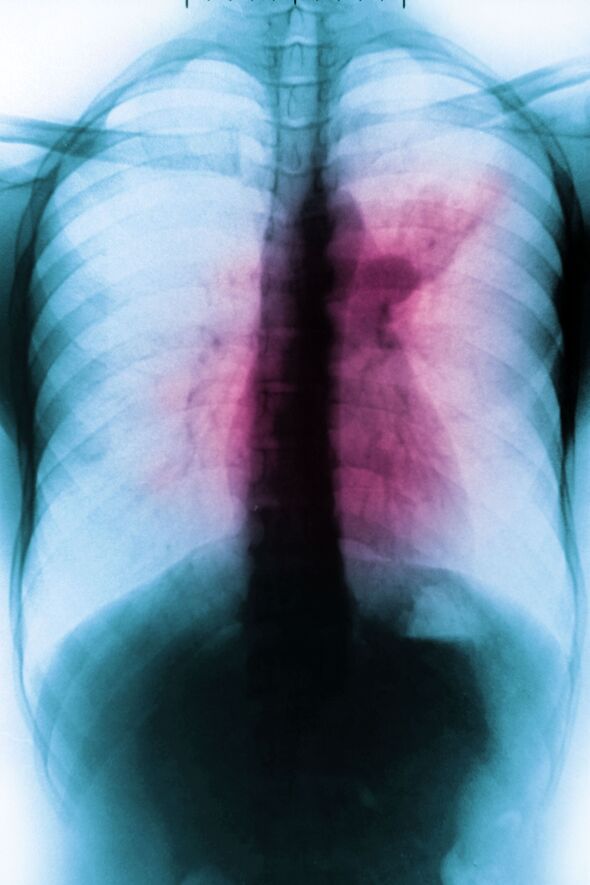

One in five cases across are going undetected as drug-resistant strains of the disease once known as the ‘white plague’ surge to seven times the global average